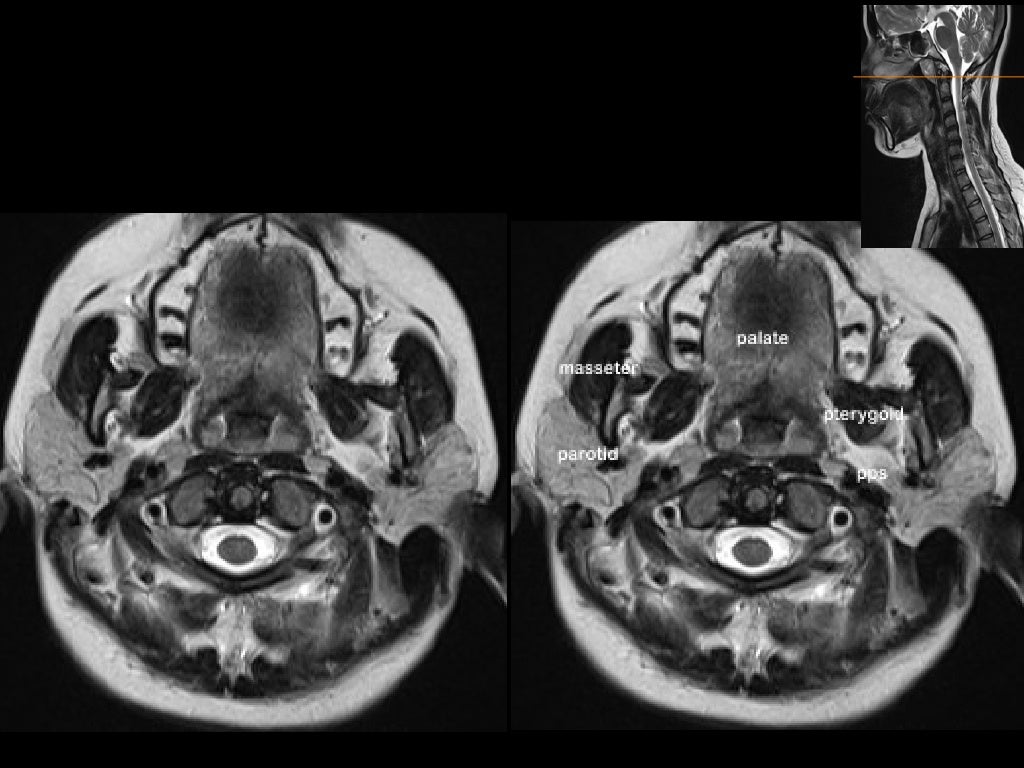

From www.slideshare.net

MRI in neck imaging Arthritis In Neck Mri It also explores the various. if your doctor suspects you have a type of arthritis, such as osteoarthritis, he or she may use a magnetic resonance imaging (mri). The discs may naturally dry. Healthcare providers sometimes call it. the article describes the symptoms, causes, and diagnosis of neck arthritis. Spondylosis is when parts of your spine begin to. Arthritis In Neck Mri.

MRI in neck imaging Arthritis In Neck Mri The discs may naturally dry. if your doctor suspects you have a type of arthritis, such as osteoarthritis, he or she may use a magnetic resonance imaging (mri). cervical refers to seven stacked bones (vertebrae) in your neck. Healthcare providers sometimes call it. the article describes the symptoms, causes, and diagnosis of neck arthritis. Two of the. Arthritis In Neck Mri.